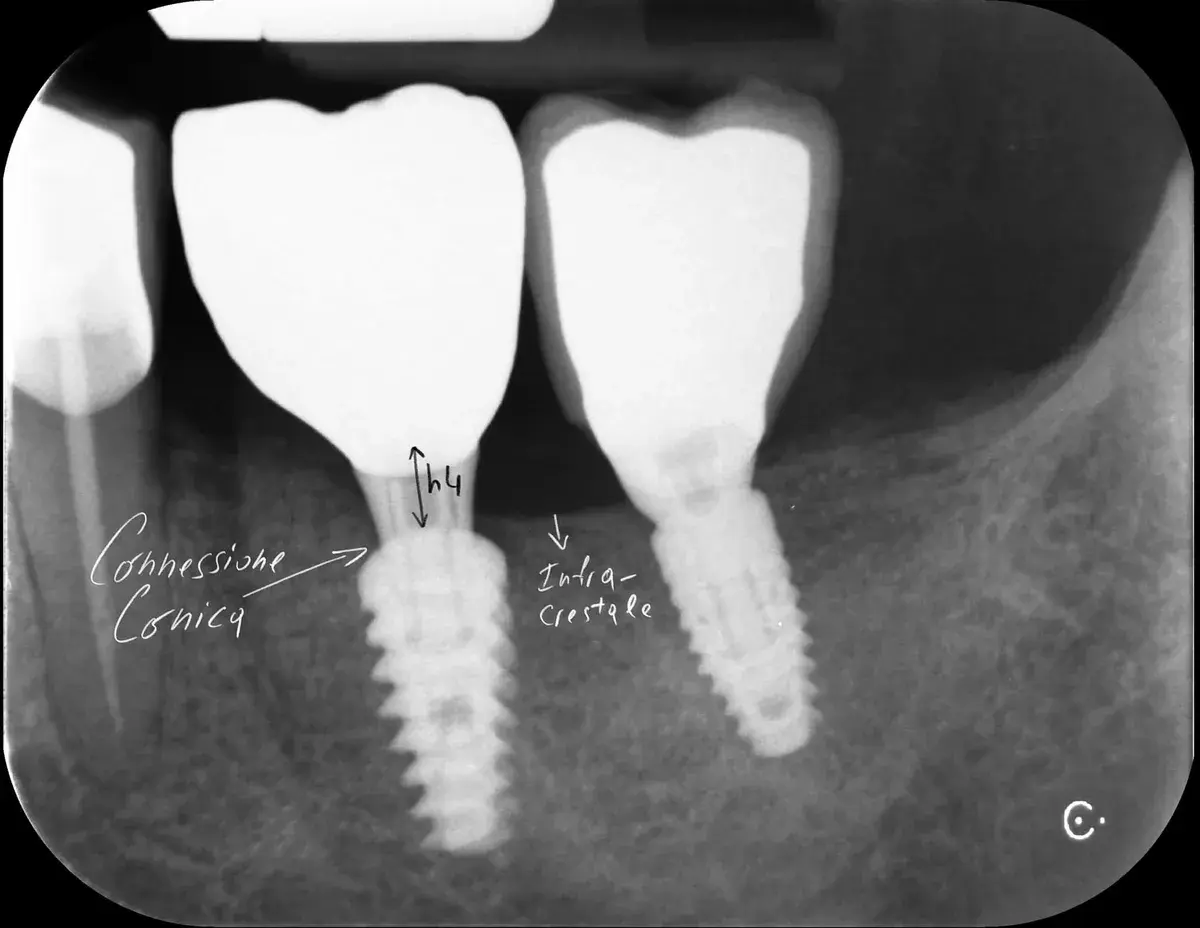

Bone-level, tissue-level, connessione conica: la profondità corretta cambia con il tipo di connessione. Perché sbagliarla causa riassorbimento osseo.

Scopri vantaggi e svantaggi delle connessioni coniche negli impianti. Cono Morse vs connessioni flat-to-flat: microgap, stabilità e preservazione ossea.